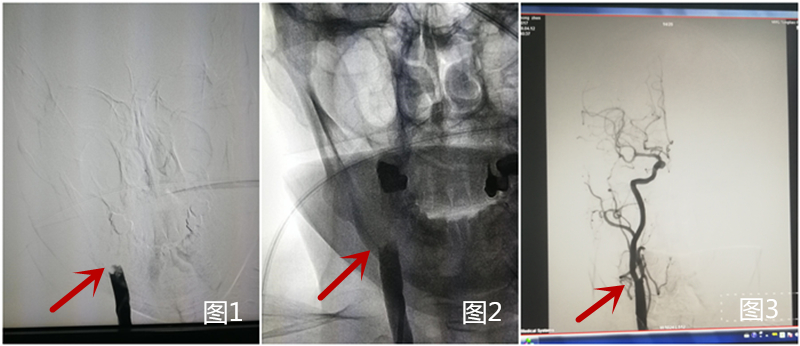

因患者到我院在发病时间窗内(<4.5h),与患者家属谈话征得其同意后,急诊立即给予阿替普酶(rt-PA)静脉溶栓,同时直接将患者送入导管室,桥接行全脑血管造影术(DSA),提示右侧颈总动脉末端闭塞(图1、2)。因患者半年前于我科行全脑血管造影术提示右侧颈内动脉未见异常(图3),此次突然发病,考虑心源性栓塞。此类栓子溶栓效果差,造影也提示溶栓无效果,积极给予支架取栓治疗。

应用抽吸方法以及支架Solitaire(6mm×20mm)取栓,可见大部分血栓取出(图4、图5),

但小部分血栓向远端移动,堵塞右侧大脑中动脉(图6),如右侧大脑中动脉不能开通,患者预后仍会较差。

于是再次用支架取栓,右侧大脑中动脉再通(图7)。

术后再次造影,可见右侧颈总动脉完全通畅(图8、图9)。